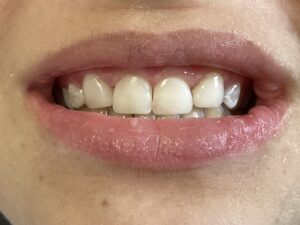

This patient arrived at my practice last week with 2 congenitally missing laterals incisors. Her orthodontist moved the canines into the position of the lateral incisors to fill the gaps but canines don’t look like incisors. They are pointy and “fat” so I told them upfront that although perfect aesthetics will not be achieved we can greatly improve the look and also remove the decay. The procedure required a single 2hr appointment and a very pleasing result was achieved with a very happy teenager leaving the practice that day. Further improvements can be done at a next visit by removing the white spots on the first premolars.